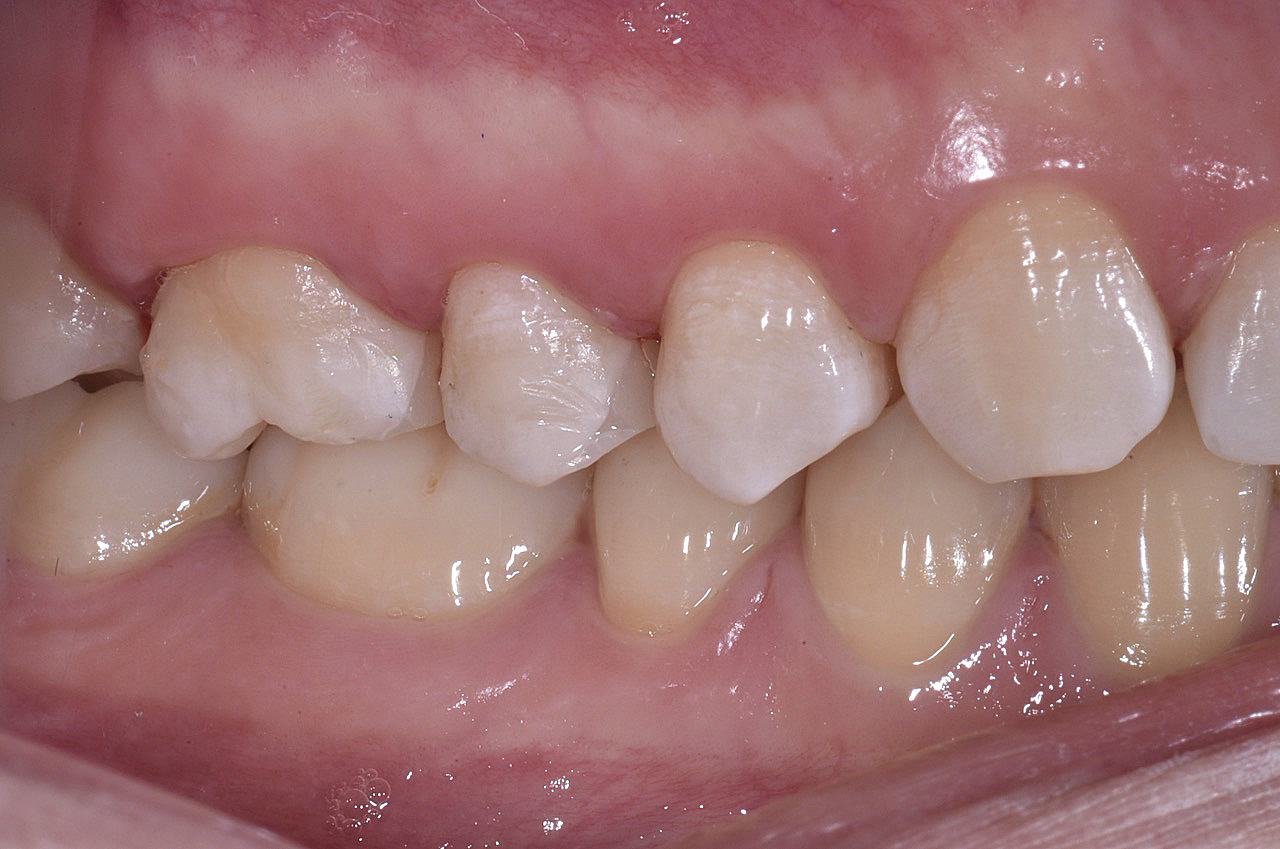

Vengono utilizzati 2 tipi di provvisori: il primo, cementato ai denti vicini, viene utilizzato dal momento dell’estrazione del dente fino ad impianto osteointegrato (circa 6 mesi); il secondo, avvitato direttamente all’impianto, ha una funzione di prova estetica ma soprattutto di guida per la maturazione dei tessuti gengivali peri-implantari portandoli verso la maturazione completa prima di posizionare la corona finale in disilicato di litio.